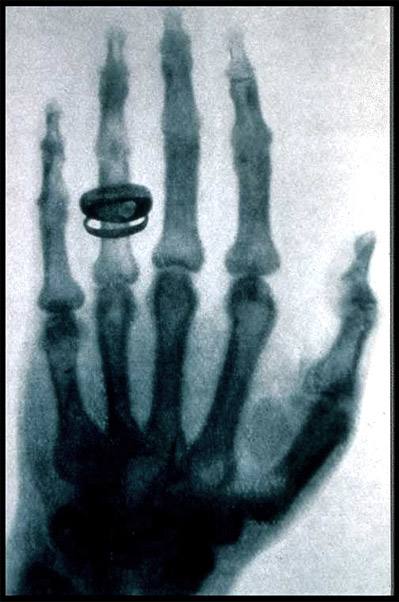

X射线是著名的伦琴发现的,它是影响医学的开端。X线发明的故事大家也都熟悉,伦琴在一个偶然的机会下从X射线现中看见了自己手的骨骼。所以说X射线主要是用来看骨头。